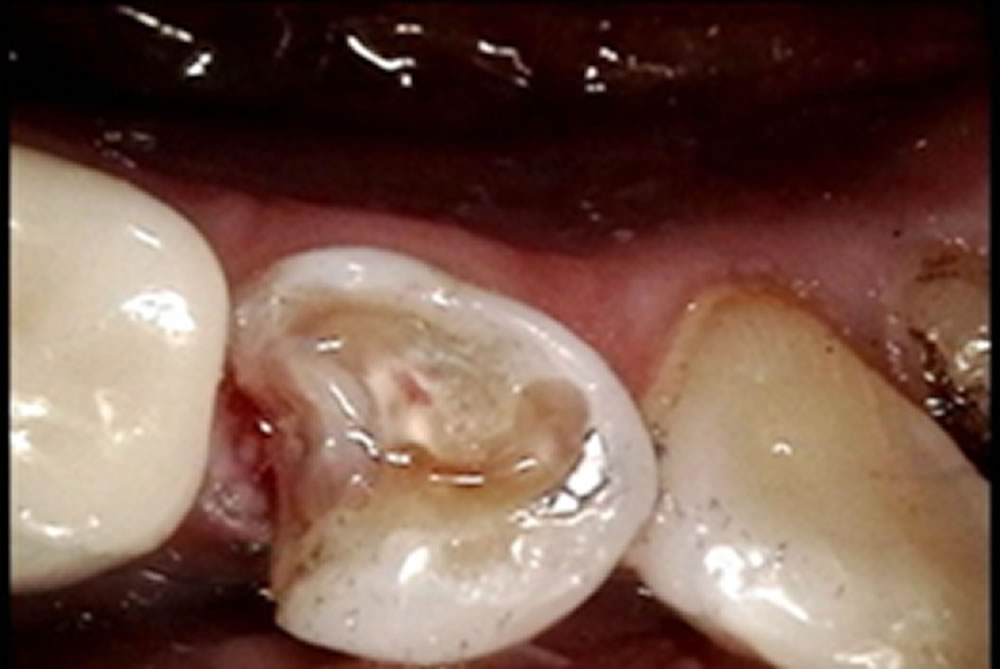

むし歯治療後にセラミックオンレーで修復した症例②

むし歯治療後にセラミックオンレーで修復した症例 こちらの患者さまはメインテナンスに通われており、レントゲン撮影をしたところ左上7番の辺縁より2次カリエスがみつかったため、治療になりました。 むし歯の除去・型取り 左上7番 […]